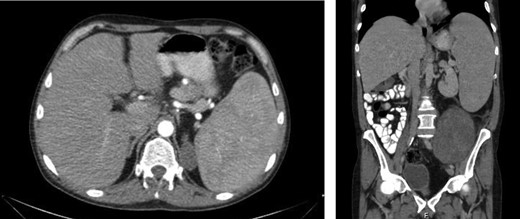

Laboratory work-up revealed a white blood cell count (WBC) of 1.0 K/ul, an absolute neutrophil count of 680, and an absolute lymphocyte count of 310. He was anemic with a hemoglobin of 6.9 g/dl. Rheumatoid factor was elevated to 180 IU/ml. An antinuclear antibody screen was positive at 1:320. Computed tomography (CT) of the abdomen and pelvis showed an enlarged spleen and a large heterogeneous mass in the left abdomen extending into the pelvis (Figs 1 and 2). A bone marrow biopsy showed abnormal CD3+ and CD8+ T-cell lymphocytosis with TCR(beta)+ and CD57+, consistent with the diagnosis of T-cell large granular lymphocytic leukemia.

Axial and coronal CT images demonstrates the large retroperitoneal mass (50 × 33 × 16 cm) displacing bowel, the left kidney, left iliac vessels and bladder to the right.

An enlarged spleen (16 × 10 × 22 cm) was identified on CT imaging obtained as part of the work-up of a palpable left abdominal mass.